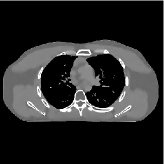

This section compares the reconstruction quality and runtime among the proposed MBIR method, PWLS-ST-, and other three MBIR methods, PWLS-EP, PWLS-DL, and PWLS-ST-. Table I shows that, for both 2D and 3D sparse-view CT reconstructions of the XCAT phantom, the proposed PWLS-ST- model outperforms PWLS-EP and PWLS-ST- in terms of RMSE. In addition, PWLS-ST- using a square transform (of size ) achieves lower RMSE than PWLS-DL using an overcomplete dictionary (of size ) for 2D sparse-view reconstructions. Fig. 3(a) and Fig. 4 show the reconstructed images for 2D and 3D phantom experiments, with different reconstruction models and different number of views. (See the corresponding error maps in the supplement.) The proposed PWLS-ST- consistently gives more accurate image reconstructions compared to other MBIR methods. Specifically, PWLS-ST- has smaller errors in the heart region (see zoom-ins in Fig. 3(a)) of 2D reconstructions than PWLS-DL and PWLS-ST-. In addition, compared to PWLS-ST-, PWLS-DL and PWLS-ST- have some ringing artifacts around the edges with high transition, e.g., edges between air and soft tissues. (See a comparison of profiles of PWLS-ST- and PWLS-ST- in the supplement.) In particular, PWLS-ST- and PWLS-DL give more visible ringing artifacts for 2D reconstruction from fewer views, and PWLS-ST- has these ringing artifacts for 3D reconstructions regardless of the number of views (see zoom-ins in Fig. 4). Table II reports runtimes of different MBIR methods in reconstructing the -views XCAT phantom scan. (FBPConvNet is a non-MBIR method and its runtime for processing a image is approximately one second with a TITAN Xp GPU.) While providing better reconstruction quality, the proposed Algorithm 1 of PWLS-ST- has shorter runtime compared to the algorithms of PWLS-DL and PWLS-ST- in Section III-A. Similar to the PWLS-EP algorithm, the reconstruction time of the PWLS-DL, PWLS-ST-, and PWLS-ST- algorithms can be further reduced by using ordered subsets [51].

Fig. 3(b) shows that when tested on the clinical scan data, the proposed PWLS-ST- method improves reconstruction quality in terms of noise and artifacts removal (e.g., see zoom-ins for soft-issue regions), and edge preservation (e.g., see zoom-ins for bone regions), compared to PWLS-EP and PWLS-ST-. Compared to PWLS-DL, PWLS-ST- achieves comparable image quality, but requires less computational complexity.

![]() |

| (a) 2D fan-beam CT experiments |

| (b) 3D axial cone-beam CT experiments |